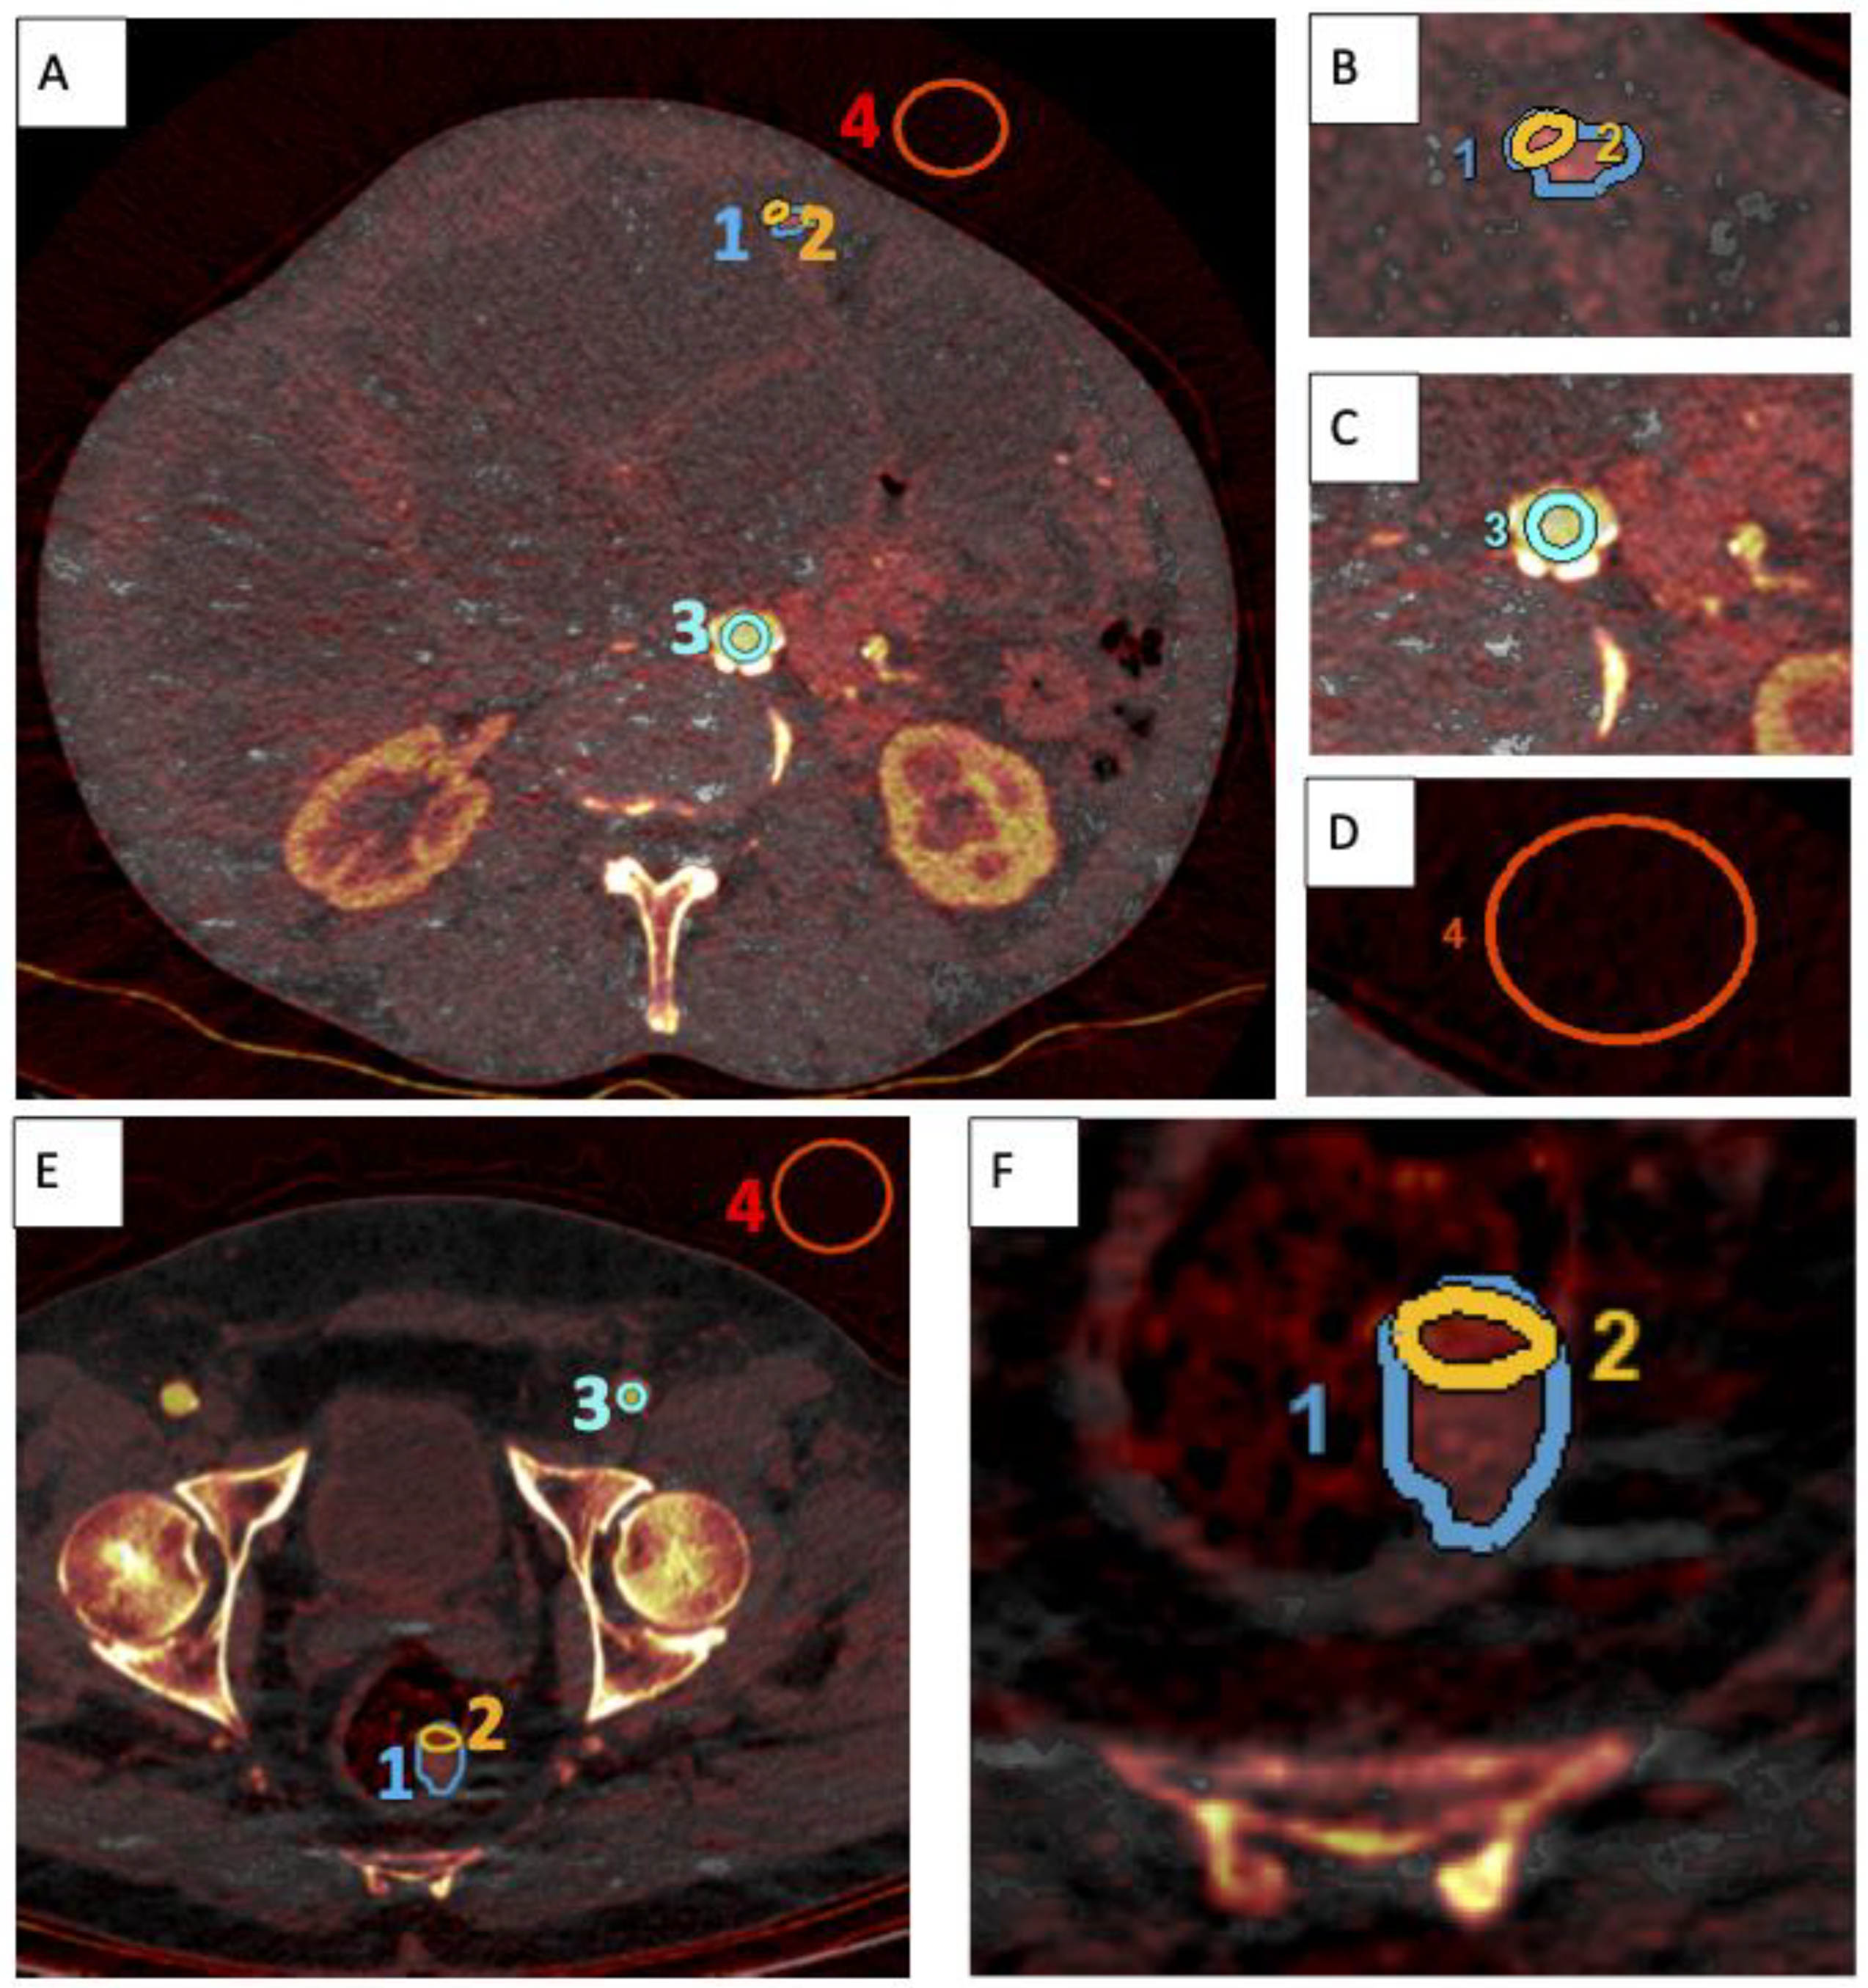

2.3. Image Analysis